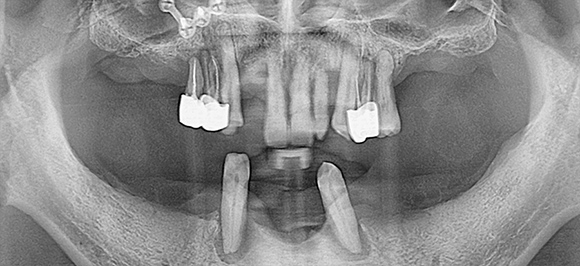

전악 임플란트 (풀케이스)

대부분의 치아를 상실했거나 발치를 해야 하는 경우

모든 치아에 임플란트를 식립하는 것이 아닌

주변까지 지지대 역할을 할 수 있는 임플란트 최소량만을 식립